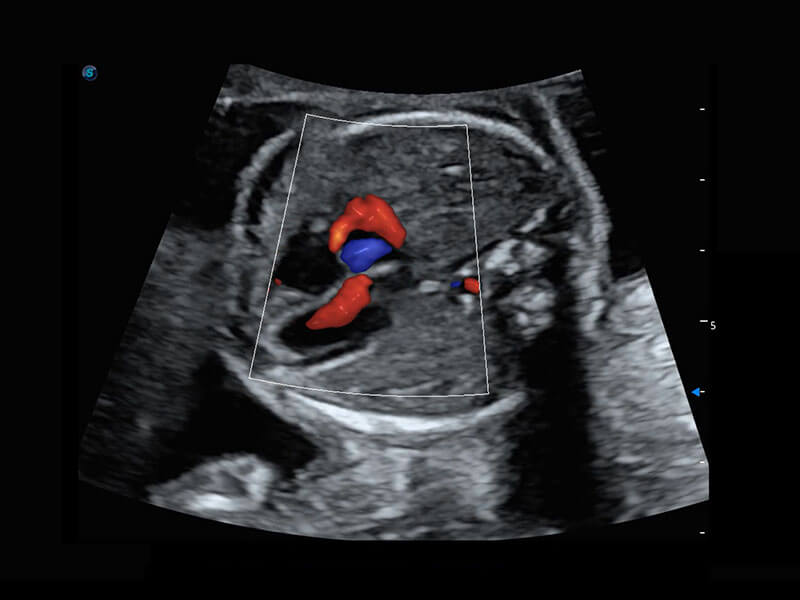

P60搭载一系列胎儿心脏成像技术,实现精细的胎儿心脏评估。

• 四腔切面

• 四腔心血流

• 右室双出口

• 胎心容积成像